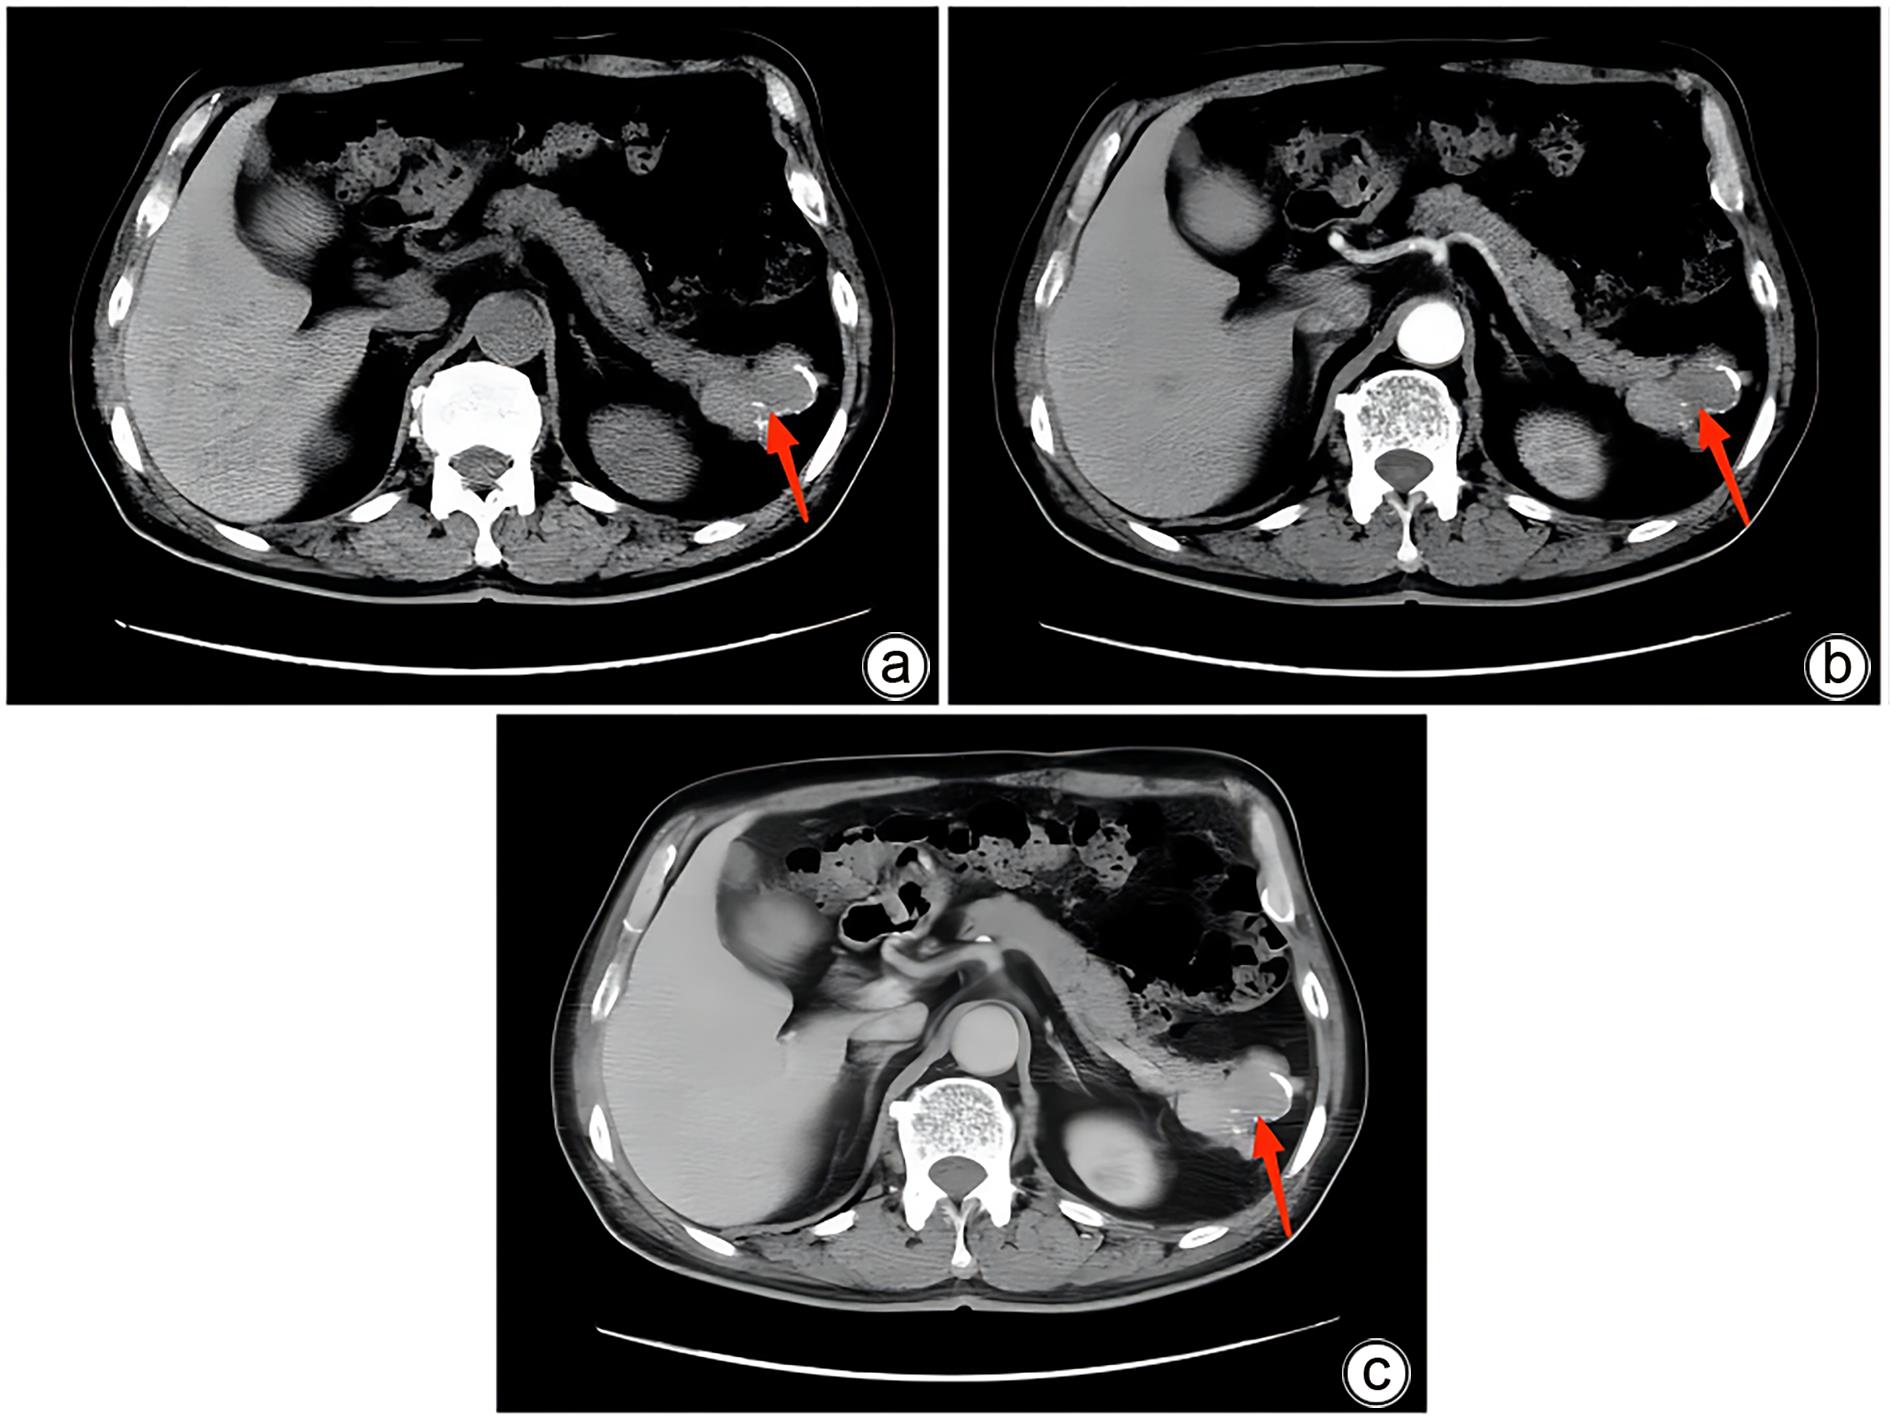

胰腺内副脾误诊2例报告

2024, 40(2): 365-368. DOI: 10.12449/JCH240223

摘要(1364) HTML (331) PDF (1188KB)(157)

摘要:

副脾是指正常脾脏以外存在的,与主脾结构相似,有一定功能的脾脏组织,其中完全被胰腺包裹的胰腺内副脾(IPAS)发生率仅为2%,因其临床症状不典型,影像学特征与胰腺神经内分泌肿瘤、胰腺实性假乳头状瘤以及其他胰腺占位性病变较为相似,临床上容易误诊。本文报道了2例分别被误诊为胰腺神经内分泌肿瘤和胰腺实性假乳头状瘤的IPAS患者,并分析误诊原因,总结诊疗经验,以期提升临床对IPAS明确鉴别诊断的认识。